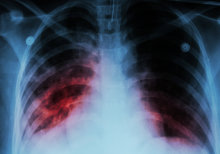

A chest x-ray showing pulmonary

TB is a bacterial infection affecting the lungs, causing cough, weight loss and fevers, and is spread through droplets from coughs and sneezes from infected patients. Diagnosing and treating the condition early is essential for the health of the patient as well as for preventing the spread of TB to others. There is therefore a need for rapid, convenient tests to rule out a TB diagnosis in suspected cases based on a blood sample.